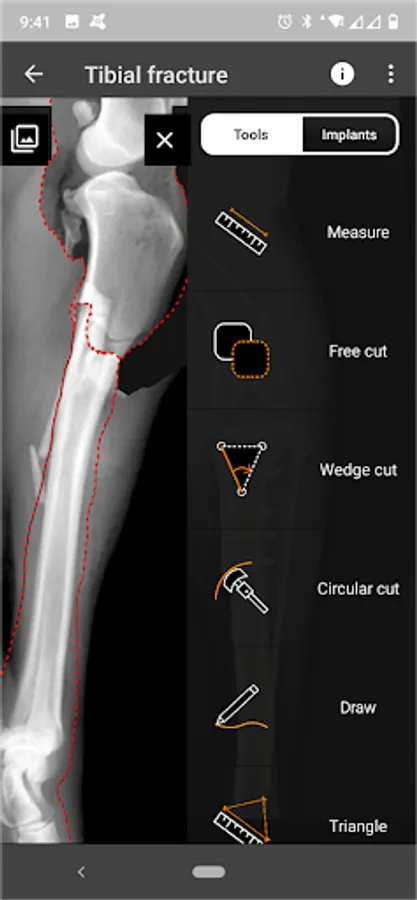

3. Tools:

a) Linear Measure.

b) Radial measure/Circle draw.

c) Angle measure/Triangle draw.

d) Free cut.

e) Wedge cut, CTWO and angular osteotomies.

f) Circular cut, TPLO.

g) Free Draw.